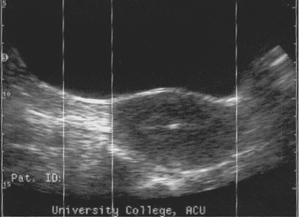

The common first step will be a dating scan between 7-10 weeks as we like to check your baby before 10 weeks . Why scan at 7 weeks? An ultrasound is performed at this stage of pregnancy to confirm your due date, confirm if you are having singles, twins or more and to visualise your baby's heart beating .

This is called the dating scan . It's used to see how far along in your pregnancy you are and check your baby's development . The scan may also be part of a screening test for Down's syndrome . Your midwife or doctor will book you a dating scan appointment .